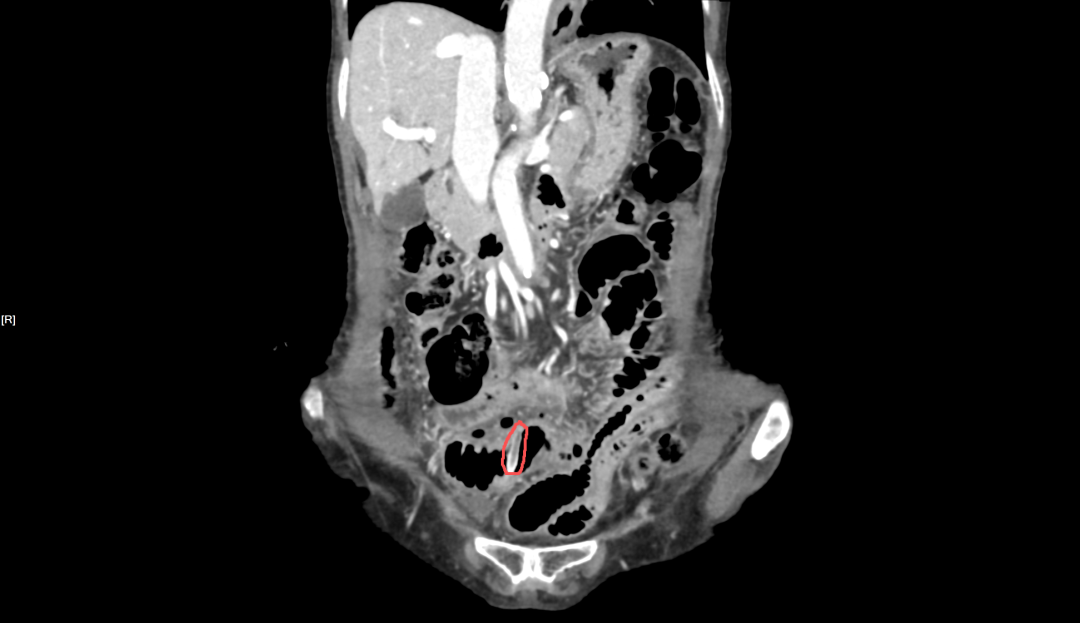

83 岁的陆阿姨就没这么幸运了。吃枣一天后,她因剧烈腹痛、腹肌紧张就诊。CT 显示,一枚 22 mm 长的枣核已刺穿小肠壁,引发急性弥漫性腹膜炎,不得不紧急手术修补肠道。

放射科医生解读:

枣核两端尖锐,呈长梭形,在影像下清晰可见。嵌顿于食管颈段者,最危险的就是刺破毗邻的颈部大血管;而一旦进入肠道,在蠕动过程中枣核尖端如同「钻头」,极易穿透肠壁,且早期症状隐蔽,发现时往往已穿孔。